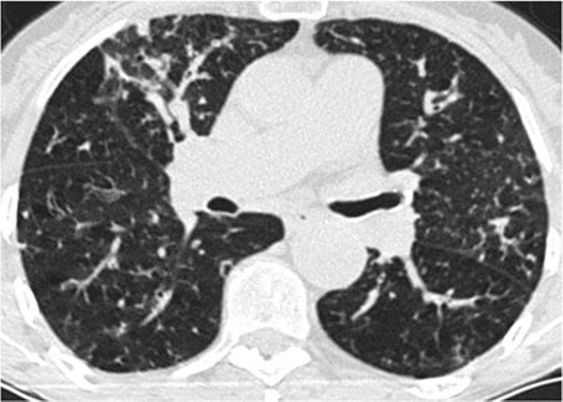

3、磨玻璃影模式

HRCT上的磨玻璃样改变被定义为不透明的薄雾影增加,并保留了支气管和血管标记。经典疾病:亚急性过敏性肺炎(HP),其特征是磨玻璃样混浊的对称斑片或弥散性双侧区域,伴有边界义不清的小叶中心型结节。有助于将亚急性HP与其他相似疾病分开的特征是,在吸气图像和气管呼气图像上,小叶区域的衰减和多血管影。磨玻璃样的最常见的鉴别疾病是呼吸性毛细支气管炎相关的间质性肺病(RB-ILD)、脱屑性间质性肺炎(DIP)和肺囊虫性肺炎。

*亚急性过敏性肺炎。 HRCT显示“磨玻璃样”改变,有少量小叶结构,没有纤维化改变

RB-ILD可表现为中度到广泛性的双侧磨玻璃影,边界不清的小叶中心型结节,支气管壁增厚。有时,在肺基部可能会出现轻微的网状结构。区分RBILD和亚急性HP的线索是RB-ILD存在上叶轻度肺气肿,HP吸烟者存在吸烟习惯的改变。

*RB-ILD 上叶水平的HRCT显示弥散的“毛玻璃样”,小叶透亮区代表伴随的小叶肺气肿。